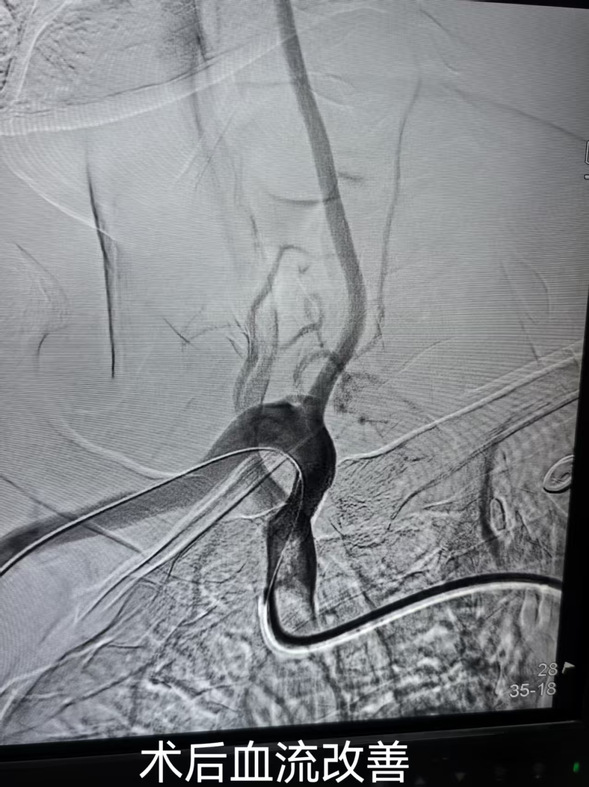

经过前期治疗,患者症状已有显著改善,但神经内六科医护团队并未放松警惕。继续为患者完善锁骨下动脉彩超及颈部CTA。结果显示:右侧锁骨下动脉盗血;右侧锁骨下动脉重度狭窄。医生们经缜密检查与分析决定,帮助患者解除潜在风险。

在综合考量患者的身体状况、病情进展及手术耐受程度等多方面因素后,任占军主任带领带领科室医生进行了术前讨论,决定为其实施锁骨下动脉支架置入术,力求消除隐患,让患者重获健康生活。

经神经内六科团队精准施治后康复出院的杨先生,专程将锦旗送至任占军主任手中。这面承载着患者深情的锦旗,不仅彰显着神经内六科团队以精湛医术解除病痛的职业素养,更诠释着现代医疗实践中不可或缺的人文温度。在任占军主任带领下,神经内六科医护团队将秉持精准治疗与暖心照护并重的诊疗理念,为群众百姓的生命健康保驾护航。